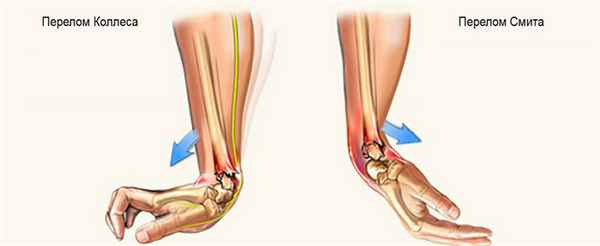

Перелом Коллеса

Один из наиболее распространенных переломов дистального отдела лучевой кости – «перелом Коллеса», при котором отломок (сломанный фрагмент) дистального отдела лучевой кости смещен к тыльной поверхности предплечья. Этот перелом был впервые описан в 1814 году ирландским хирургом и анатомом, Авраамом Коллесом.

Перелом Смита

Роберт Смит описал подобный перелом лучевой кости в 1847 году. Воздействие на тыльную поверхность кисти считается причиной такого перелома. Перелом Смита – это противоположность перелома Коллеса, следовательно, дистальный отломок смещается к ладонной поверхности.

- Перелом Смита (сгибательный перелом). Причиной травмы служит падение на вытянутую руку, на ее тыльную сторону. Кость ломается и при этом происходит смещение костных отломков в сторону ладони.

- Перелом Коллеса (разгибательный перелом). Повреждение случается при падении человека на ладонь, наблюдается смещение костных отломков в сторону большого пальца и тыльной поверхности кисти.